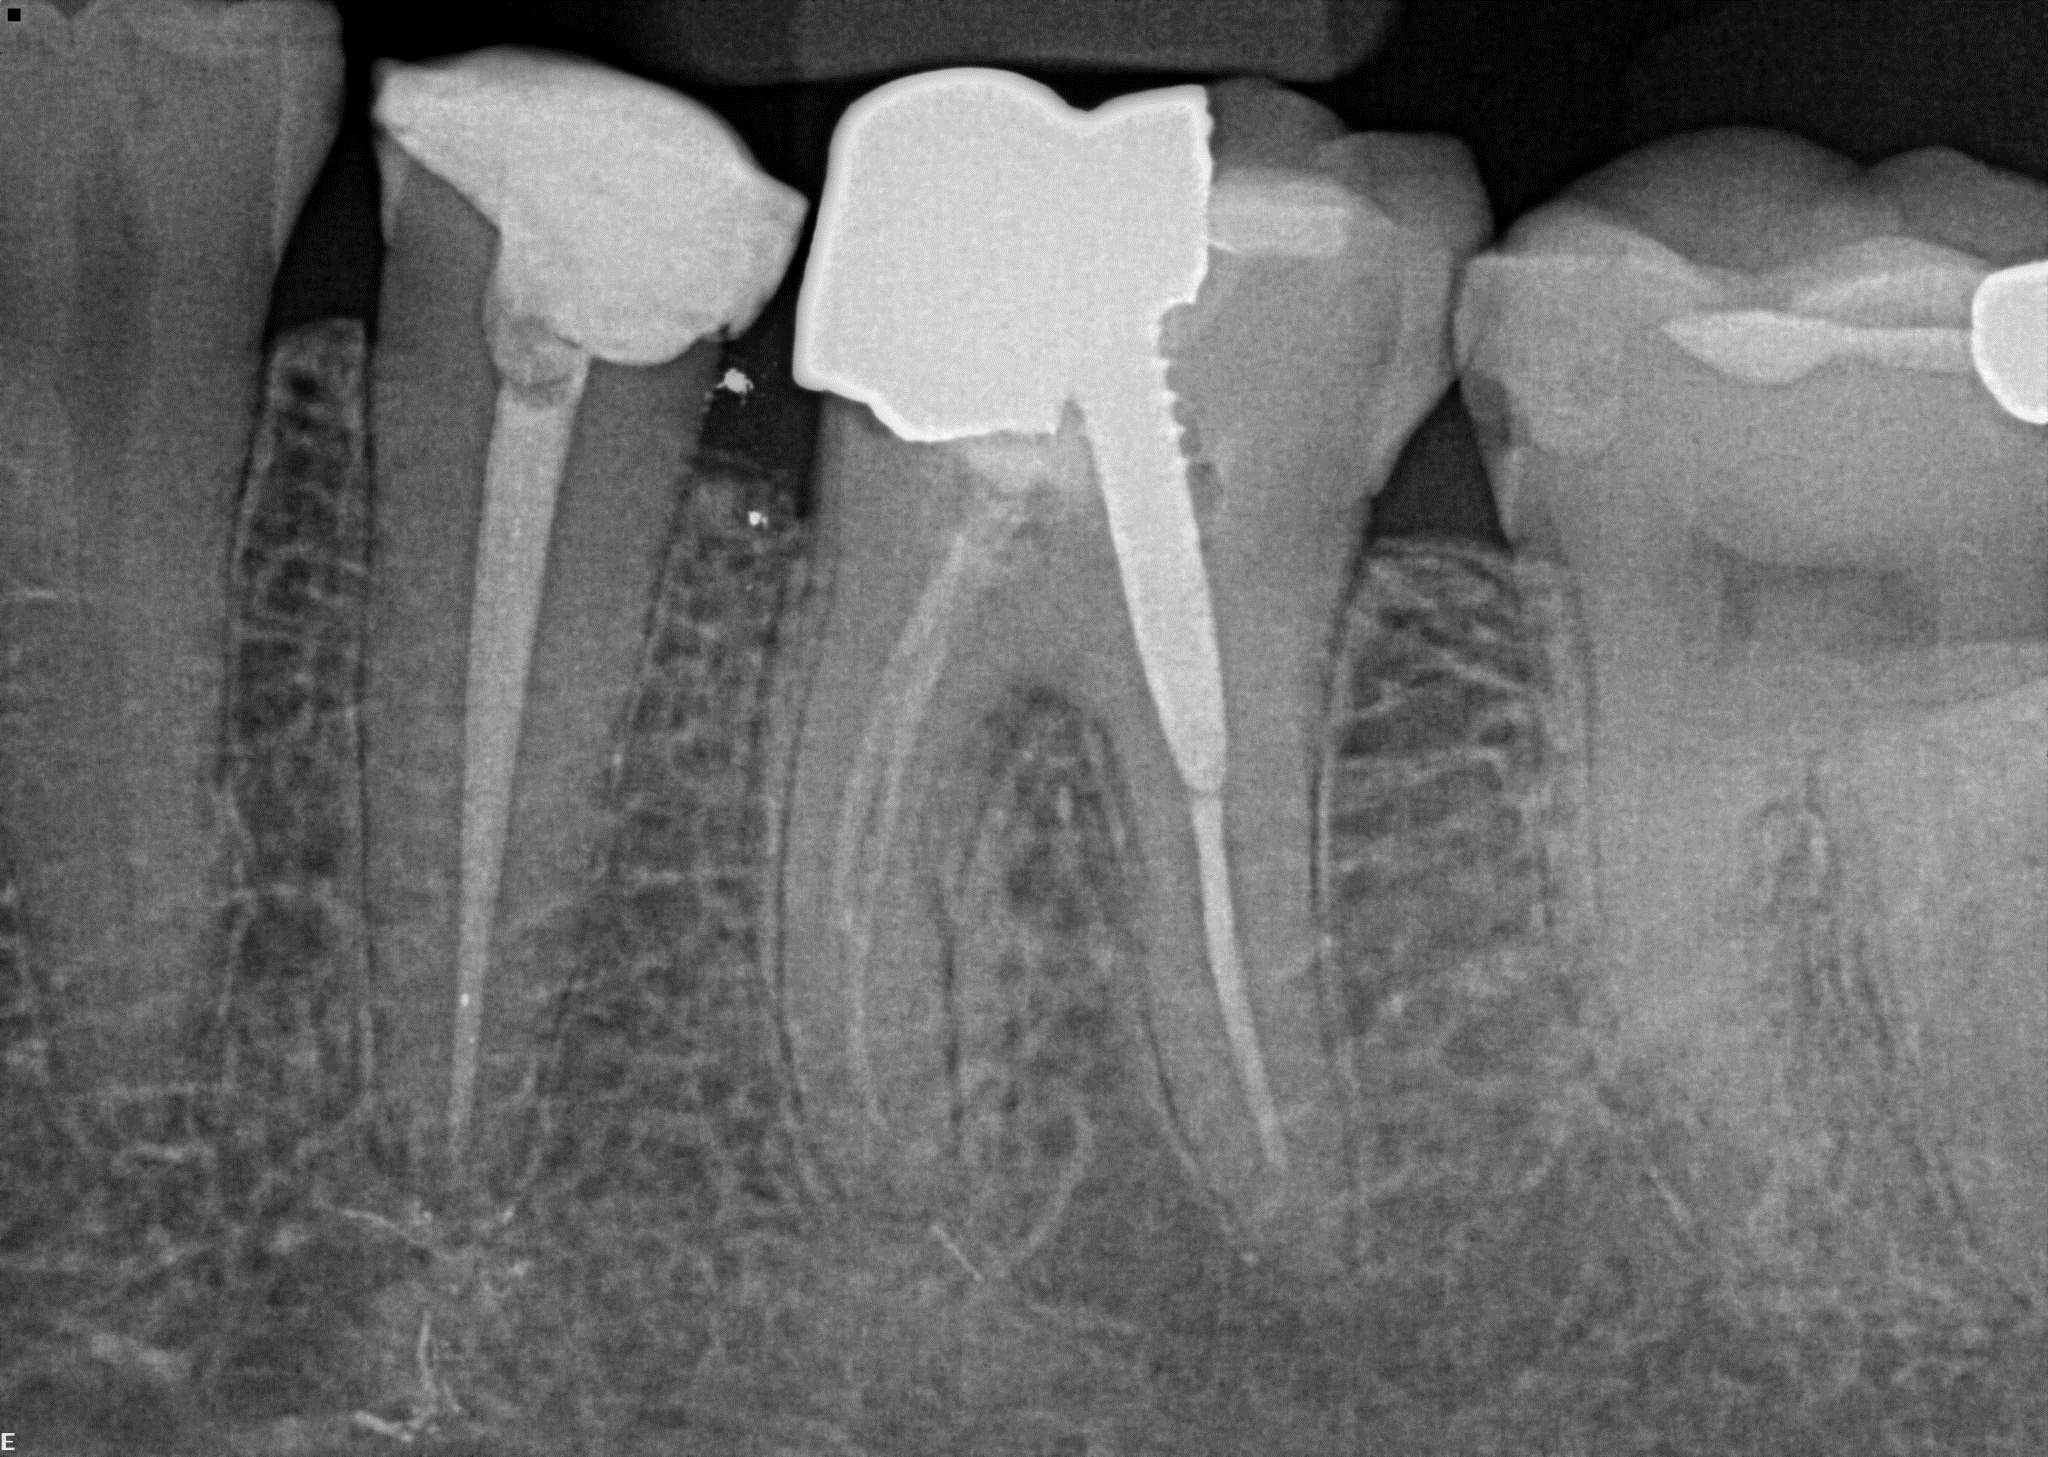

8. (Select ONE OR MORE correct answers)

Which of the following describe(s) the endodontic treatment of tooth 3.6?